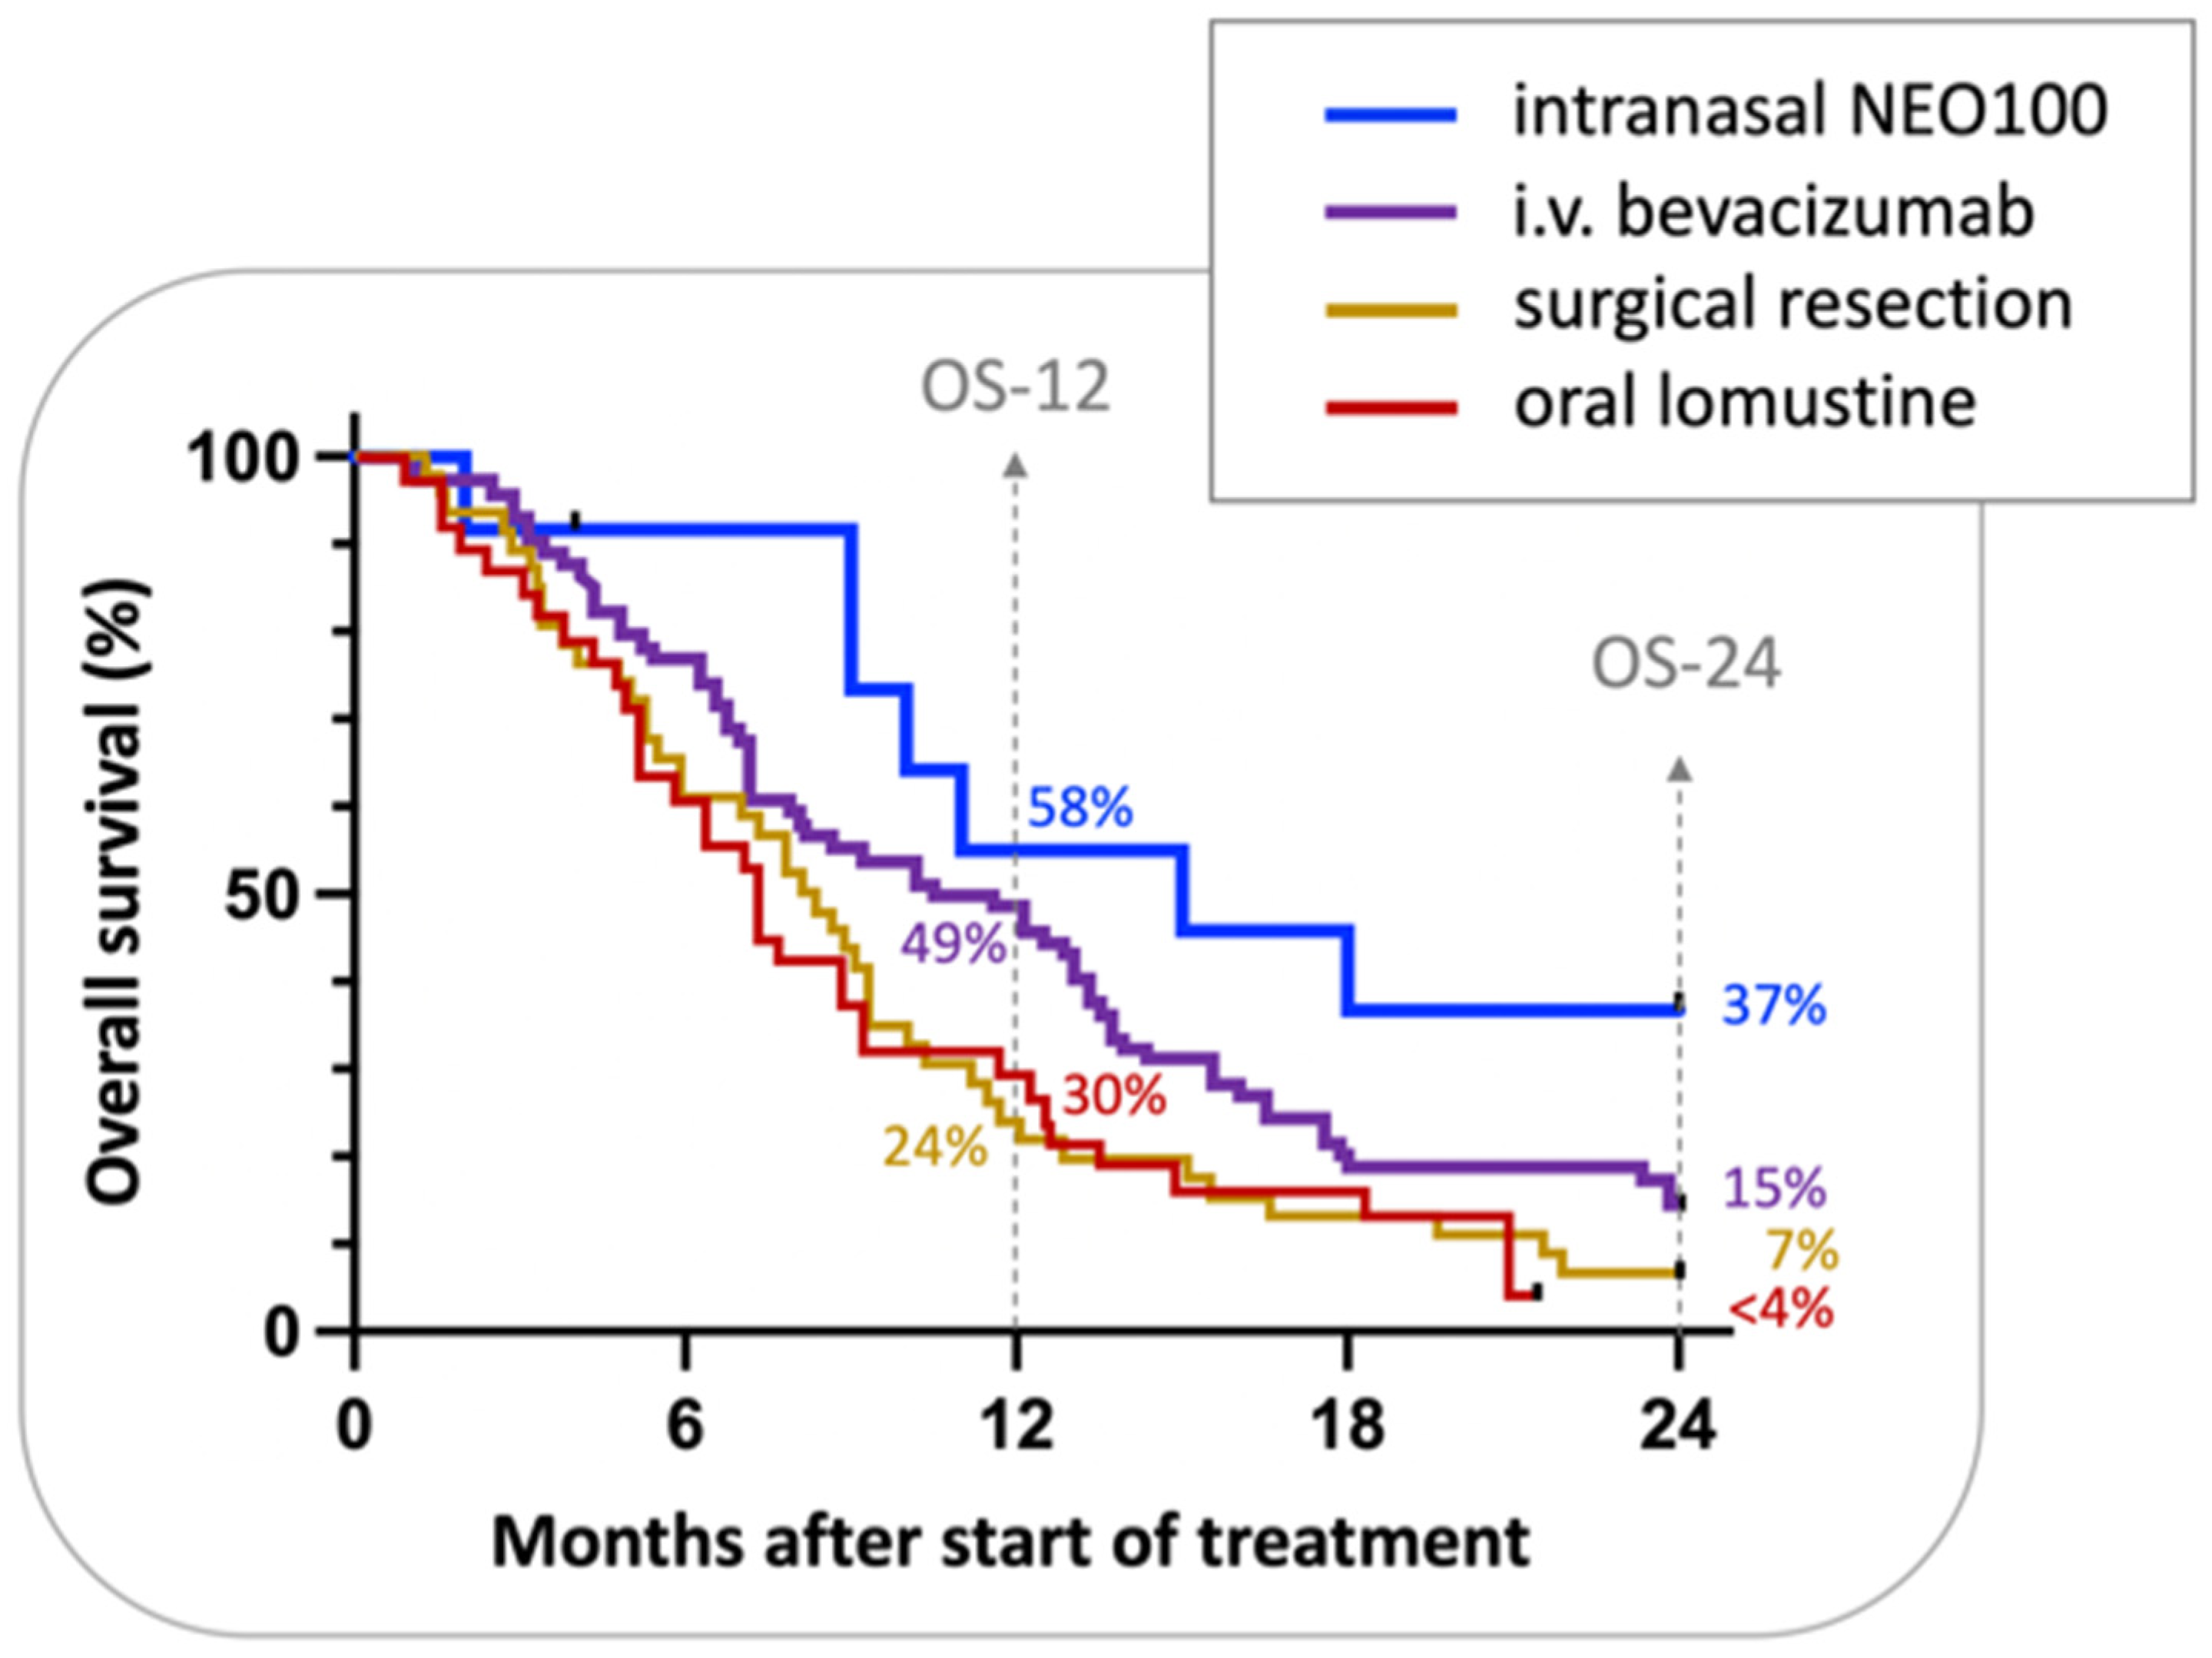

- Schönthal, A.H.; Peereboom, D.M.; Wagle, N.; Lai, R.; Mathew, A.J.; Hurth, K.M.; Simmon, V.F.; Howard, S.P.; Taylor, L.P.; Chow, F.; et al. Phase I trial of intranasal NEO100, highly purified perillyl alcohol, in adult patients with recurrent glioblastoma. Neuro-Oncol. Adv. 2021, 3, vdab005. [Google Scholar] [CrossRef]

- Barker, F.G., II; Chang, S.M.; Gutin, P.H.; Malec, M.K.; McDermott, M.W.; Prados, M.D.; Wilson, C.B. Survival and functional status after resection of recurrent glioblastoma multiforme. Neurosurgery 1998, 42, 709–720, discussion 720–703. [Google Scholar] [CrossRef] [Green Version]

- Batchelor, T.T.; Mulholland, P.; Neyns, B.; Nabors, L.B.; Campone, M.; Wick, A.; Mason, W.; Mikkelsen, T.; Phuphanich, S.; Ashby, L.S.; et al. Phase III Randomized Trial Comparing the Efficacy of Cediranib As Monotherapy, and in Combination With Lomustine, Versus Lomustine Alone in Patients With Recurrent Glioblastoma. J. Clin. Oncol. 2013, 31, 3212–3218. [Google Scholar] [CrossRef] [Green Version]

- Brandes, A.A.; Finocchiaro, G.; Zagonel, V.; Reni, M.; Caserta, C.; Fabi, A.; Clavarezza, M.; Maiello, E.; Eoli, M.; Lombardi, G.; et al. AVAREG: A phase II, randomized, noncomparative study of fotemustine or bevacizumab for patients with recurrent glioblastoma. Neuro-Oncology 2016, 18, 1304–1312. [Google Scholar] [CrossRef]

- Desjardins, A.; Herndon, J.E., II; McSherry, F.; Ravelo, A.; Lipp, E.S.; Healy, P.; Peters, K.B.; Sampson, J.H.; Randazzo, D.; Sommer, N.; et al. Single-institution retrospective review of patients with recurrent glioblastoma treated with bevacizumab in clinical practice. Health Sci. Rep. 2019, 2, e114. [Google Scholar] [CrossRef] [PubMed] [Green Version]

- Ghiaseddin, A.; Peters, K.B. Use of bevacizumab in recurrent glioblastoma. CNS Oncol. 2015, 4, 157–169. [Google Scholar] [CrossRef]

- Weller, M.; Le Rhun, E. How did lomustine become standard of care in recurrent glioblastoma? Cancer Treat. Rev. 2020, 87, 102029. [Google Scholar] [CrossRef] [PubMed]